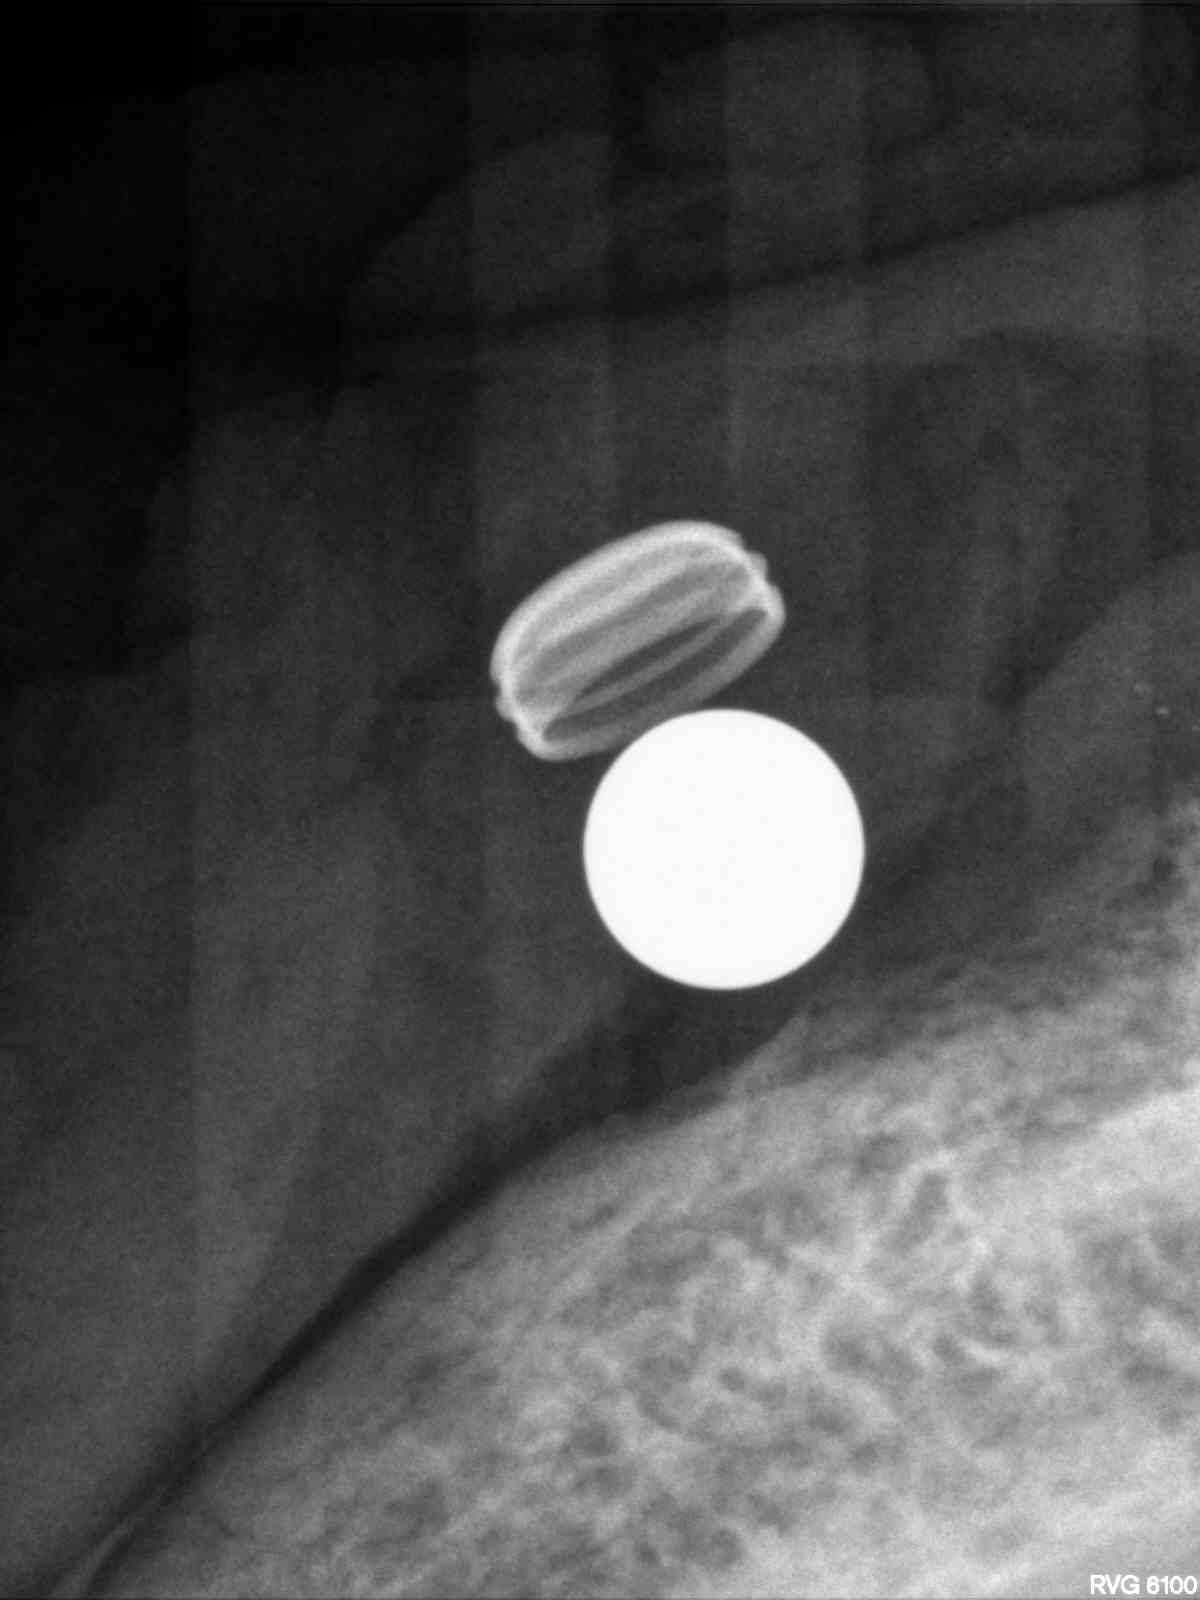

Legacy 3 3.7mm 11.5mm

implanted r4

Implant for locator retained denture

Immediate #21 Legacy 3 4.2x13mm

Legacy 3 #7 3.7mm 13mm